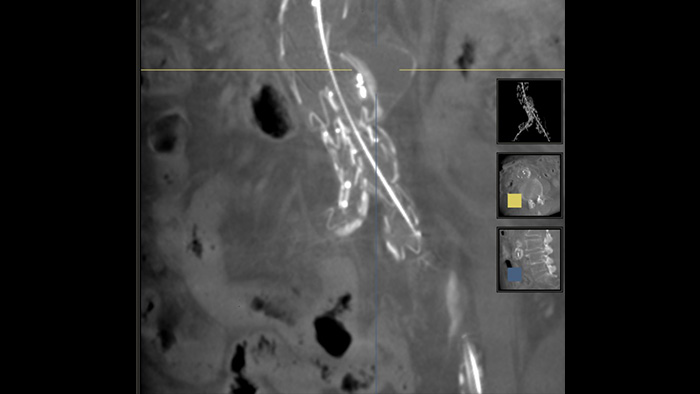

SmartCT Soft Tissue ist eine Röntgen-Erfassungstechnik, die eine CT-artige Darstellung des Weichgewebes in Relation zu anderen Strukturen erzeugt. Sie kann direkt am Tisch über den Touchscreen gesteuert werden. Mit den CT-artigen Bildern können Weichgewebe, Knochenstrukturen und Stent-Platzierung vor, während und nach interventionellen Verfahren beurteilt werden. Diese Technik ist besonders hilfreich, um nach (komplexen) EVAR-Verfahren Komplikationen zu erkennen.